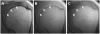

Tissues, such as bone, tendon, and ligaments, contain a high fraction of components with "short" and "ultrashort" transverse relaxation times and therefore have short mean transverse relaxation times. With conventional magnetic resonance imaging (MRI) sequences that employ relatively long echo times (TEs), there is no opportunity to encode the decaying signal of short and ultrashort T2 /T2 * tissues before it has reached zero or near zero. The clinically compatible ultrashort TE (UTE) sequence has been increasingly used to study the musculoskeletal system. This article reviews the UTE sequence as well as various modifications that have been implemented since its introduction. These modifications have been used to improve efficiency or contrast as well as provide quantitative analysis. This article reviews several clinical musculoskeletal applications of UTE.